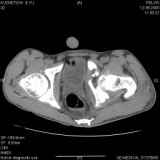

Уважаемые коллеги! Хотелось бы услышать совет по тактике лечения представлленого больного.

Поступил после лечения в одном изотделений области. Травма 2,5 месяца назад.

После выведения

из шока был произведен остеосинтез перелома бедра, предплечья, до перевода к нам проводилось

вытяжение по оси шейки бедра за стержень, введенный в большой вертел. На сегодня деформация

ригидна, клинически мобильности не определяется.